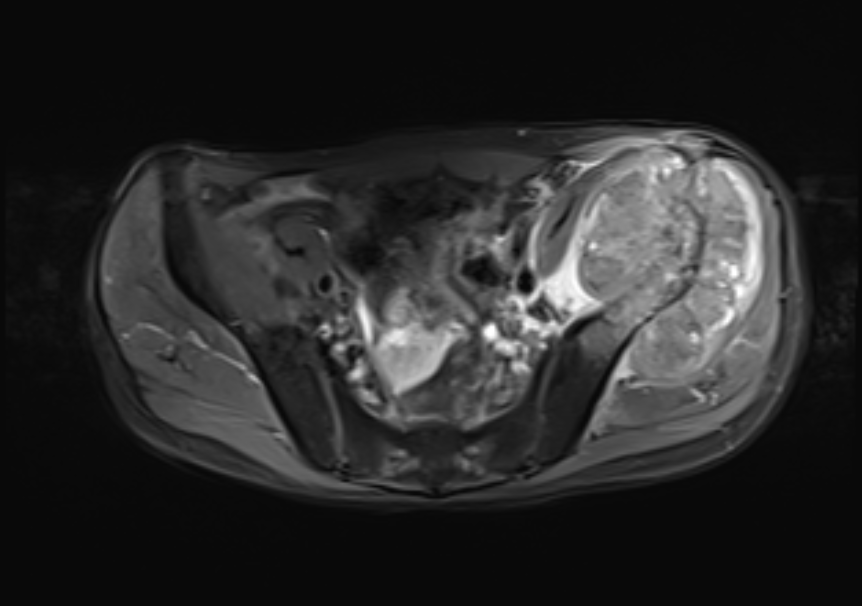

髋关节MR检查图像

图片

MR表现:

左侧髂骨骨质破坏,累及髋臼,形成巨大软组织肿块,其最大径大致约 10.6cmx7.6cmx7.6cm;与邻近肌肉相比:T2WI肿块下部呈稍高信号,外 上部呈高信号,T1WI呈等高信号,其中可见斑点状高信号;DWI高b值, 肿块下部呈不规则高信号。瘤周肌肉可见水肿;左侧腰大肌前移。膀胱直肠窝可见少许液性信号影。

MR诊断:

1、左侧髂骨改变,结合病史,考虑转移瘤。